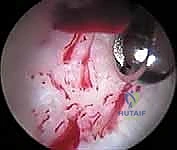

بناءً على ما تم تشخيصه، يقوم الجراح بتنفيذ الإجراءات التالية باستخدام أدوات آلية دقيقة (Shavers, Burrs, Radiofrequency probes):

* تنظيف الشفا (Labral Debridement): إذا كان النسيج الممزق تالفاً جداً ولا يمكن خياطته، يتم تشذيبه وإزالة الأجزاء المتهتكة لتخفيف الألم ومن